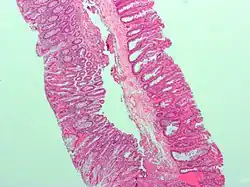

| Tubular adenoma | 2% at 1.5 cm[12] | Low to high grade dysplasia[13] | Over 75% of volume has tubular appearance.[14] |

Adenomas

Neoplastic polyps of the bowel are often benign hence called adenomas. An adenoma is a tumor of glandular tissue, that has not (yet) gained the properties of cancer.

The common adenomas of the colon (colorectal adenoma) are the tubular, tubulovillous, villous, and sessile serrated (SSA).[18] A large majority (65–80%) are of the benign tubular type with 10–25% being tubulovillous, and villous being the most rare at 5–10%.[9]

Micrograph of a tubular adenoma, the most common type of dysplastic polyp in the colon

Micrograph of a tubular adenoma, the most common type of dysplastic polyp in the colon -

Micrograph of a tubular adenoma – dysplastic epithelium (dark purple) on left of image; normal epithelium (blue) on right. H&E stain.

Micrograph of a tubular adenoma – dysplastic epithelium (dark purple) on left of image; normal epithelium (blue) on right. H&E stain. -